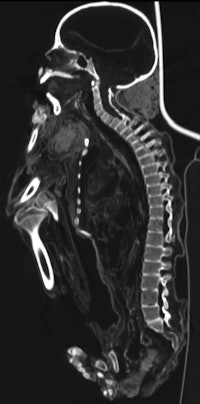

"First, the axial scans were evaluated, using different ranges of window width and window level parameters to identify structures with different densities," the authors wrote. Next, to virtually remove the bandages, "preset reconstruction algorithms for soft tissues with varying window width parameters were used to obtain the progressive elimination of external layers with a density lower than that of dried skin, starting from the bandages."

Among other findings, conditions identified in the bones included an occipital osteoma, as well as osteoarthritis or mild tuberculosis-related changes of a sacroiliac joint. A severe spondylodiscitis, a lytic lesion in the sacral bone, and erosions at one tarsal joint were also observed, which most likely represent severe manifestations of skeletal tuberculosis, the researchers noted.

Indications of pulmonary tuberculosis were also found. "Five of eight mummies showed several small intrapulmonary or mediastinal calcifications, such as those seen typically in pulmonary tuberculosis," the authors wrote.